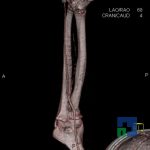

- Diagnosticul fracturilor:

- Unice

- Multiple

- Cu înfundare